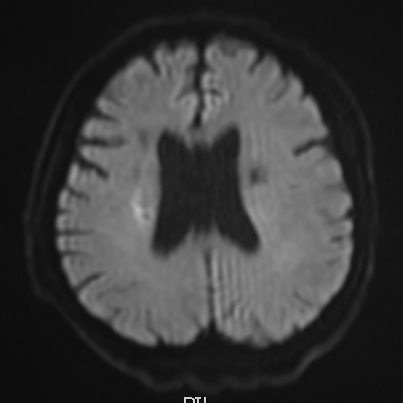

脑梗塞

新鲜脑梗塞